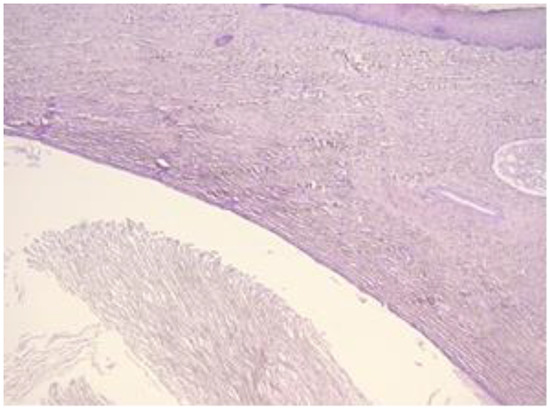

The exo-cervix was found to be lined by a non-keratinised stratified epithelium (squamous epithelium) showing a distinct basal layer, but the appearance of atypical keratinocytes was noted, with some of them showing koilocytotic atypia with sharply outlined perinuclear vacuoles, dense and irregular staining peripheral cytoplasm and an enlarged, modified nucleus (Figure 1). The p16 expression showed a positive nuclear/cytoplasmic expression in the cervical mucosa (Figure 2).

Figure 1. Exo-cervix showing a distinct basal layer and atypical keratinocytes (HE staining, 40×).